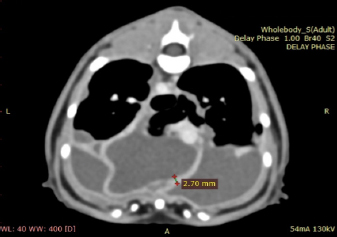

A blood test (Table 1) on day 6 revealed a mild-to-moderate non-regenerative anemia, neutrophilia, monocytosis, and mild hypoalbuminemia 19 g/l (RR; 22–40). A CT scan (Fig. 3) of the chest was carried out to investigate the radiographic opacities and rule out any potential penetrating foreign body. A large amount of dependent free fluid was noted, with Hounsfield units of about 30, implying a highly cellular effusion. Multiple septations were present with marked contrast enhancement and up to 3-mm-thick walls separating fluid into larger cavities, particularly caudal to the heart (Fig. 3). Fluid took up about 60% of the pleural cavity displacing lungs dorsally and limiting their expansion, and there was mild ventral parietal pleural contrast enhancement. No evidence of inciting pathology, visible foreign bodies, or penetrating traumatic wounds were identified. The radiographic nodular radiopacities were suspected to be previous pockets of effusion.

Fig. 3. Day 6: coronal view of a CT scan of the thorax showing contrast-enhancing pleural septations within pyothorax.